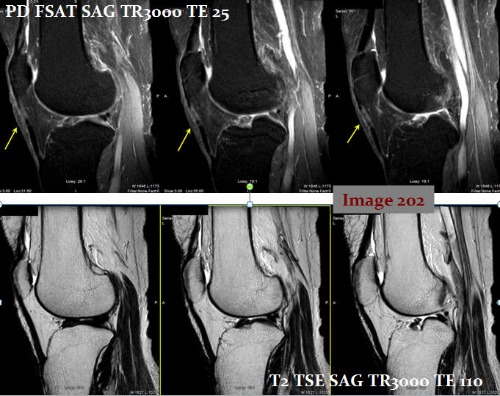

The yellow arrows in Image 202 are pointing to an artifactual increase in signal within the supraspinatus tendon. This is known as:

A. Magic angle

B. Dielectric

C. Aliasing

D. Annefact